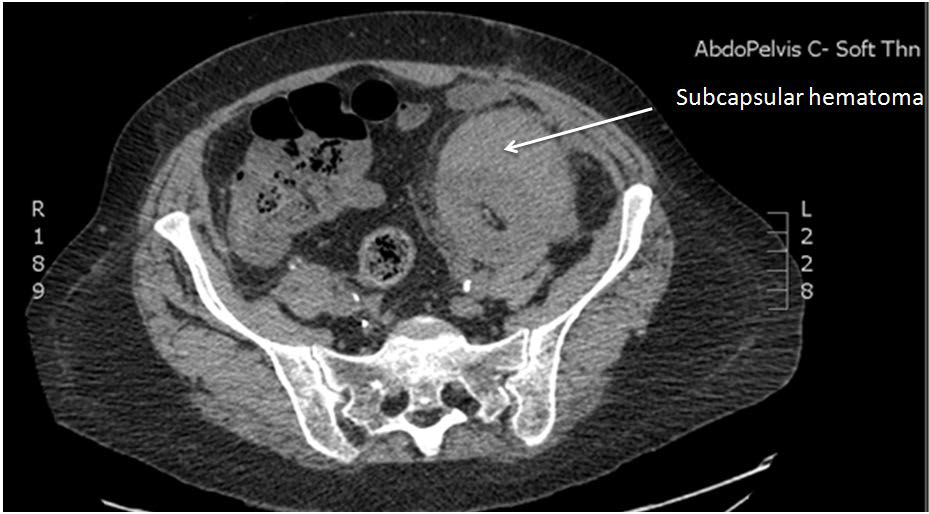

Figure 3: CT image showing subcapsular haematoma in the transplanted kidney.

figure 3